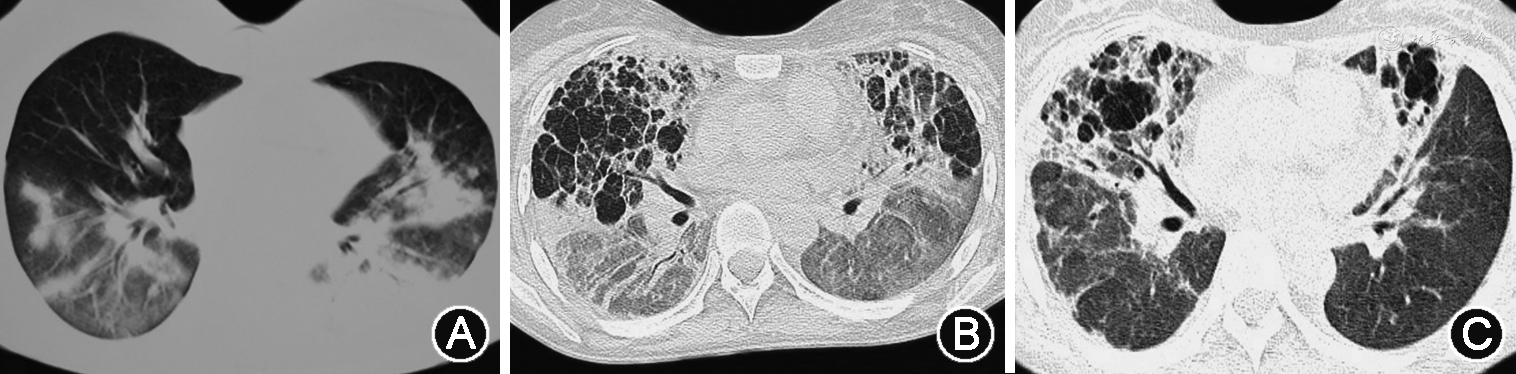

2. 危重病例:多表现为大片状或弥漫性病灶,在重症病例影像表现基础上,以实变为主,也可以合并肺不张和“白肺”改变[13,15, 16, 17,23,28, 29],少数病例可见胸腔积液[25, 26]。病程多进展较快,需要机械通气,继发纵隔气肿、皮下气肿及气胸[11,23,30](图4、5)。同时也常常合并其他感染及并发症,如肺栓塞等[11,30]。

甲型H1N1流感重症肺炎进展快、吸收消散亦快。吸收往往从肺实变开始,表现为肺阴影变淡和密度不均,以及不同程度的纤维化改变[36](图5)。GGO及实变1周内出现,2周达到峰值,4周及以后吸收或消失[23]。纤维化在发病第1周即可出现,在发病第3周达到峰值,然后缓慢下降。对于病程较长的危重症患者,恢复吸收相对较慢[37](图5)。黎淑娟等[38]将甲型H1N1流感重症肺炎病变CT动态变化分成3种类型:先进展后吸收型、先吸收和进展并存后吸收型以及逐渐吸收型。